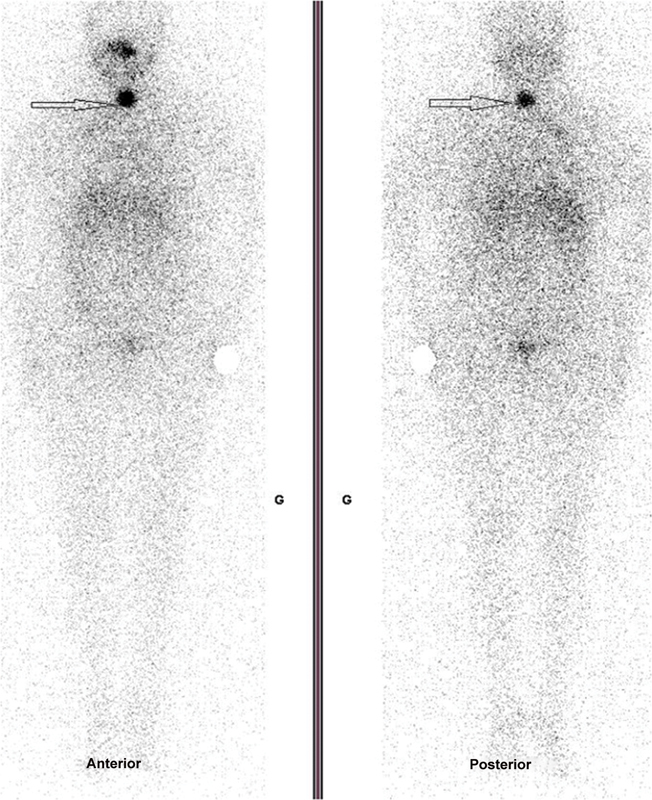

Differentiated thyroid cancer (DTC) is the most common endocrine cancer and its outcome is usually favorable. Its basic treatment is well codified, but its monitoring is much less. The value of thyroglobulin (Tg) is one of the main elements for monitoring DTC, while the use of iodine scintigraphy is becoming less recommended. In this case report, we discuss a clinical situation where a patient presented differentiated thyroid metastatic lesions confirmed by biopsy, uptaking radioactive iodine, with undetectable levels of Tg (in the absence of autoantibodies). We discuss the various hypotheses explaining this clinical situation, the potential advantages of performing periodic iodine scintigraphy in some intermediate and high-risk patients and report the documented clinical benefit of radioiodine therapy.